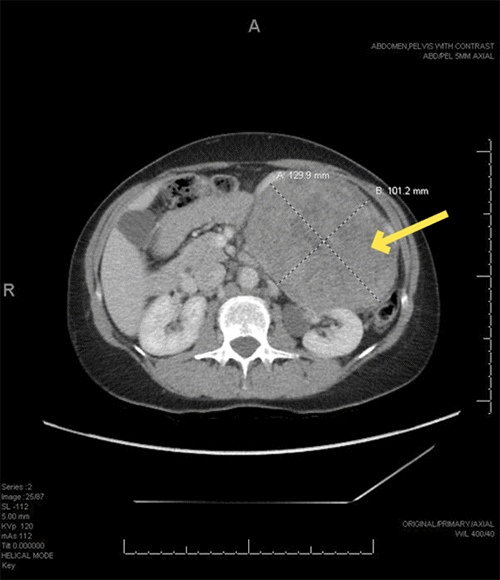

The patient was referred to the surgical oncology service for preoperative evaluation and operative planning for the excision of the mass. Given the size and symptomatic nature of the mass, a decision was made to pursue a more radical surgical excision instead of a percutaneous biopsy. Preoperative computed tomography of the abdomen and pelvis was obtained to assess the anatomic planes for resection because the MRI images performed at the previous medical facility were not readily available (Figure 2).

Figure 2. CT with IV Contrast Images of Mass. Published with Permission

A) Axial at its largest dimensions; images were used for preoperative planning and visualization of planes of dissection